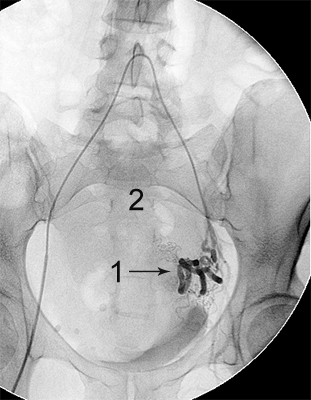

міома матки до емболізації    міома матки після емболізації

Розширена звивиста ліва маткова артерія (1),

вузол лейоміоми матки (2)

Після емболізації частками: маткова артерія

збережена (1), лейоміома не контрастується (2).